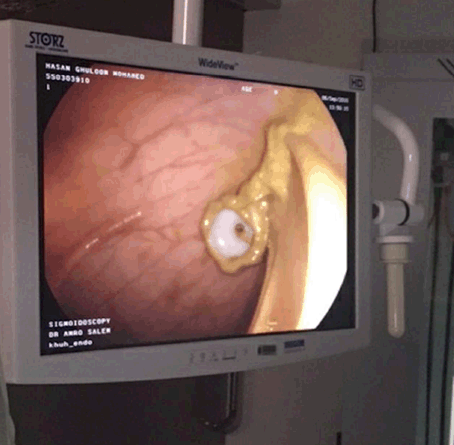

As part of initial management, a cecostomy tube was inserted that failed to produce contents and the abdominal girth was increasing daily, despite six hourly flushing of the rectal tube. Patient was advised surgery, with all necessary risks and benefits are explained. However, the patient and his family refused the procedure. Plan to perform a percutaneous endoscopic colostomy was implemented. The procedure was done under sedation using midazolam 1 mg intravenous and fentanyl 0.025 mg intravenous. Partial sigmoid volvulus was noted on endoscopy, for which detorsion was performed. Under the guidance of two operators, trans-illumination was performed with the lighted tip of the endoscope pressing outward against the abdominal wall to identify point of insertion. Local anesthetic was injected into the skin and using the percutaneous endoscopic gastrostomy (PEG) kit, a needle was used to enter the colon under direct vision. The wire was grasped by a snare and then the PEC tube was pulled and trailed into the colon and out through the abdominal wall using the Ponsky technique. The PEC tube was inserted at 35 cm from the anal verge, with confirmation of placement via endoscopy (Figure 5).

Figure 5: Endoscopic confirmation.